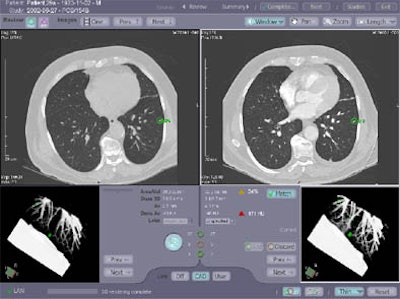

| Original and follow-up CT lung scans are seen pre-alignment (above) and post-alignment (below) in a prototype CAD scheme that tracks nodules and measures their growth between exams. Workstation view (bottom) shows apparent growth of one nodule by 34% (39.0 cu mm to 52.2 cu mm) at three-month follow-up. Images of R2 Technology's ImageChecker system courtesy of Haili Chui, Ph.D. |

The system works by automatically overlaying the original and follow-up studies, then warping them together using an anatomic landmark-guided algorithm. ImageChecker measures nodule volume, and calculates the rate of change including the doubling rate.

The results showed that for each volume, the relative bias and corresponding standard deviation of CAD volume measurements remained under 2% (from -2% to +2%). No statistically significant change was seen as a result of varying exposure levels, Chui said.

Next, using a database of patient scans acquired from 1.5 to 13 months apart, the system was instructed to find each nodule, create a correspondence with its counterpart in the later exam, and measure the volume difference, if any, in the size of nodules. The system detected 24/28 nodules (85.7%) in both initial and follow-up scans, and 26/28 (92%) were detected in at least one of the scans. The system determined the correct correspondences in 100% of the scans in which the nodules were detected in both exams. There were an average of 2.5 false-positives per case.

"You can see in this nodule 52% growth over two months," he said of one case. "Another nodule in this (same patient) showed no growth at all...and so basically the system helps the efficiency of the workflow in nodule detection, tracking, and measurement," he said. FDA approval is pending.